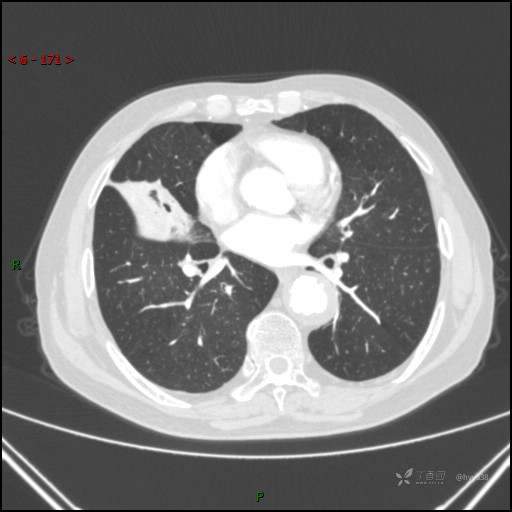

胸部CT肺窗